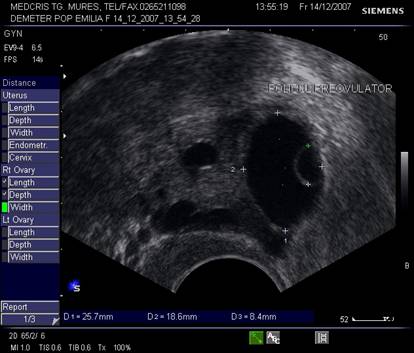

Fig. nr.371. Folicul selectat ziua a XI a de ciclu menstrual, la ecografia transvaginala

Fig. nr.372. Folicul preovulator , in care se remarca

cumulus oophorus ( sageata, eco transv.)

Dupa ziua a 5-7, un folicul ovarian devine dominant , fata de ceilalti ce devin atretici. In ziua 10 -a - 11-a foliculul depaseste 12 mm diametru. Cresterea foliculara de 2 - 3 mm/zi ne duce la un folicul preovulator de cca 21 mm diametru (24 - 26 mm). Doi foliculi dominanti au fost identificati in 10% din ciclurile spontane [8].

Deoarece foliculii sunt ovoidali, diametrul mediu conteaza pentru foliculometria, dupa masurarea a 3 diametre si impartirea la 3.[6]